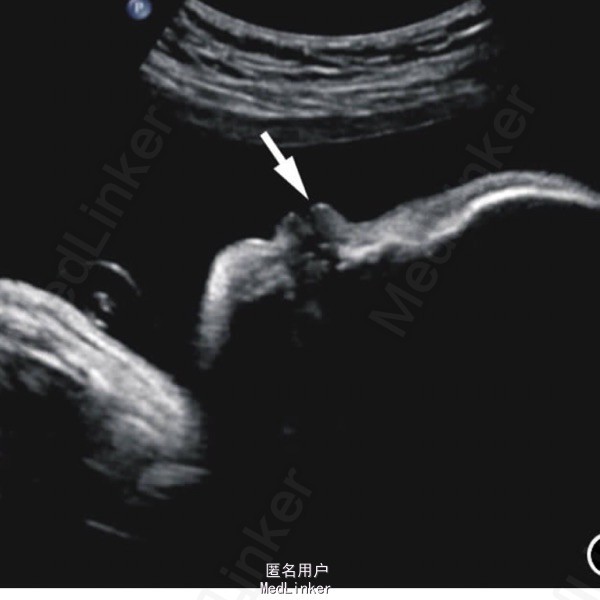

患儿女,1h,因胎膜早破剖宫产娩出。生后无鼻,张口呼吸。其母孕期彩超提示鼻骨未探及。

查体:体重2715g,前额较宽大,眼距正常,面部未见外鼻结构。 辅查:染色体未见异常,torch阴性

诊断:鼻缺如畸形 处理:本例为单纯鼻缺如,完善颅内及其他脏器检查均未见异常。家属因经济原因未行人工鼻移植。患儿病情稳定后出院。